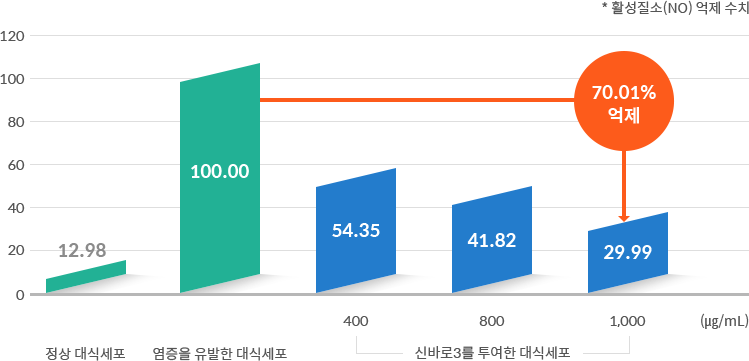

강력한 항염 효과② - 염증 인자 최대 70% 억제

염증을 유발시킨 쥐의 대식세포에 신바로 약침을 투여한 결과, 염증의 매개체인 활성질소의 생성이 효과적으로 억제되

었습니다.

었습니다.

- 연구기관 : 자생척추관절연구소, 서울대학교 천연물과학연구소 연구팀

- 저널명 : Mediators of Inflammation(염증성 매개물질을 전문분야로 하는 SCI급 국제학술지) 2018년 4월호

- 논문명 : The Anti-Inflammatory Effects of Shinbaro3 Is Mediated by Downregulation of the TLR4

Signalling Pathway in LPS-Stimulated RAW 264.7 Macrophages